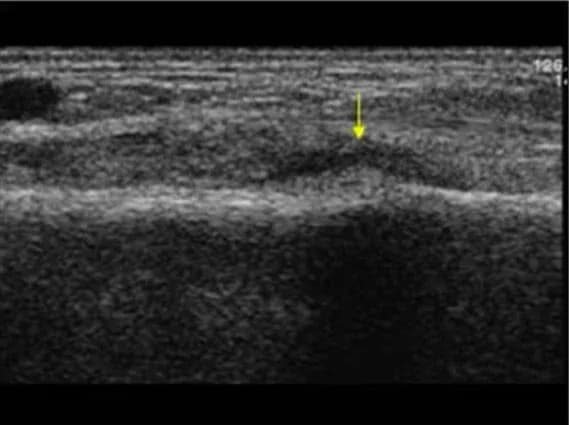

Fraktur am Unterschenkel

Die unterbrochene Knochenlinie ist deutlich sichtbar.